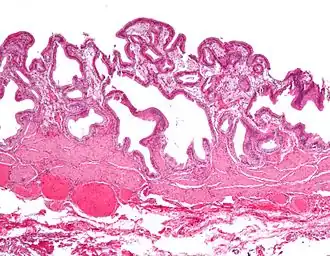

| Micrografia da colesterolose da vesícula biliar. Mancha de H&E. | |

Na patologia cirúrgica, vesícula biliar de morango, mais formalmente colesterolose da vesícula biliar e colesterolose de vesícula biliar, é uma alteração na parede da vesícula biliar devido ao excesso de colesterol.[1]

O nome vesícula biliar de morango vem da aparência tipicamente pontilhada da superfície da mucosa, em um exame grosseiro, que se assemelha à aparência de um morango.

Colesterolose da vesícula biliar (Imagem grosseira). Micrografia da colesterolose da vesícula biliar.

Micrografia da colesterolose da vesícula biliar. Micrografia da colesterolose da vesícula biliar.

Micrografia da colesterolose da vesícula biliar. Micrografia da colesterolose da vesícula biliar.

Micrografia da colesterolose da vesícula biliar.